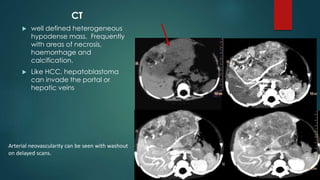

CT

 well defined heterogeneous

hypodense mass. Frequently

with areas of necrosis,

haemorrhage and

calcification.

 Like HCC, hepatoblastoma

can invade the portal or

hepatic veins

Arterial neovascularity can be seen with washout

on delayed scans.